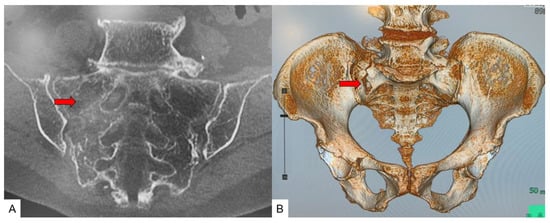

3.3. SIF Fracture Pattern

3.4. Typical SIF Case